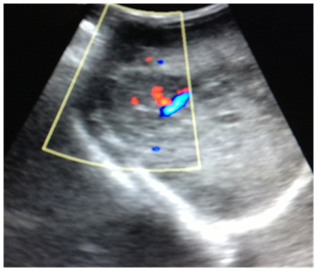

At abdominal ultrasonography, it was noted heterogeneous image, irregular, ill-defined, with Doppler vascularity in the right hepatic lobe (Figure 2). It is also visualized, at the right adrenal region a rounded image of imprecise limits, predominantly hypoechoic, with calcifications and Doppler vascularization, measuring about 3.7x2.1 cm in its largest axis (Figure 3).

Figure 3 Abdominal ultrasound demonstrates at the right adrenal region, a rounded image of imprecise limits, with points calcifications and Doppler vascularization.